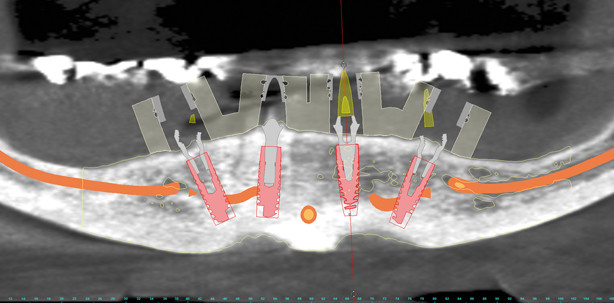

Nach der digitalen Übermittlung der DVT-Daten aus der chirurgischen Praxis an das zahntechnische Labor erfolgten die Konvertierung und Segmentierung des DICOM-Datensatzes durch die Software (SimPlant®, Materialise Dental GmbH, Deutschland; Abb. 2). In diesem Zuge erfolgte die Darstellung der N. alveolaris beidseits und das virtuelle Extrahieren der beiden noch vorhandenen Wurzelreste zur Darstellung der zu erwartenden Extraktionsalveolen. Mittels des Optical Scan Moduls wurde ein konventionelles Situationsmodell der Ausgangssituation digitalisiert und in den Planungsdatensatz eingelesen (Abb.3). Die notwendige Referenzierung erfolgte anhand der noch vorhandenen Zähne. Diese Vorgehensweise ermöglicht es, vollständig auf eine Bariumsulfat-Scanprothese zu verzichten und somit nicht nur eine Behandlungssitzung einzusparen, sondern auch die Gesamtkosten zu senken. Die im DVT fehlenden Zähne wurden in diesem Fall über das Modell der Ist-Situation – mit der vorhandenen herausnehmbaren Prothese – digitalisiert. Sollte die aktuelle Versorgung jedoch in ästhetischer oder funktioneller Hinsicht insuffizient sein, kann ebenfalls mit einem digitalen oder analogen Wax-up gearbeitet werden. Unser Planungskonzept im Team sieht vor, dass die Zahntechnik eine prothetische Vorabplanung erarbeitet. Hierbei werden die Implantate unter prothetischen Gesichtspunkten positioniert und mit realistischen Abutments versehen. Hierfür bietet die verwendete Software originalgetreue STL-Daten für eine Vielzahl der am Markt befindlichen Implantatsysteme an. Innerhalb der Software lässt sich die Planung sowohl als errechnetes dreidimensionales Bild als auch in verschiedenen zweidimensionalen Schnittbildern anschauen. Im Anschluss trifft sich das Team aus chirurgischem und prothetischem Implantologen und Zahntechniker per Onlinesitzung (Teamviewer) zur Verfeinerung des Planungsvorschlages. Gemeinsam kann so eine optimale Planung erfolgen, indem sowohl der chirurgischen als auch der prothetischen Sichtweise Augenmerk geschenkt wird. Ferner ist allen Teammitgliedern von Anfang an der gesamte Workflow bekannt und alle Teammitglieder adaptieren gemeinsam den Therapieplan. Die dreidimensionale Planung schafft so einen chirurgisch und prothetisch vorhersagbaren Behandlungsablauf, der aus unserer Sicht alternativlos ist. Aufgrund der vorhandenen Knochensituation und den Extraktionsalveolen wurde die virtuelle Implantatpositionierung durchgeführt (Abb. 4). Dieses Konzept sieht die Abwinkelung der distalen Implantate um bis zu 30 Grad vor, mit dem Ziel, das prothetische Stützfeld zu vergrößern. Die initiale Angulation der Implantate gleichen speziell entwickelte, angulierte Abutments aus.

Nach Extraktion der Wurzelreste erfolgt die vollständig schienengestützte Implantation über die stereolithografisch gefertigte Bohrschablone (ExpertEase™; Abb. 5 und 6). Diese Schiene weist einen definitiven Tiefenstopp auf und ermöglicht dem chirurgischen Implantologen, alle Schaftlochbohrungen sowie die Aufbereitung des Bohrstollens navigiert durchzuführen. Ferner ist das Inserieren des Implantates durch den entsprechenden Guide möglich (Abb. 7). Die Genauigkeit der stereolithografisch gefertigten Übertragungsschablonen ist anderen Verfahren überlegen. Gerade im Hinblick auf Sofortversorgungen hat sich diese Verfahrenstechnik bewährt.12